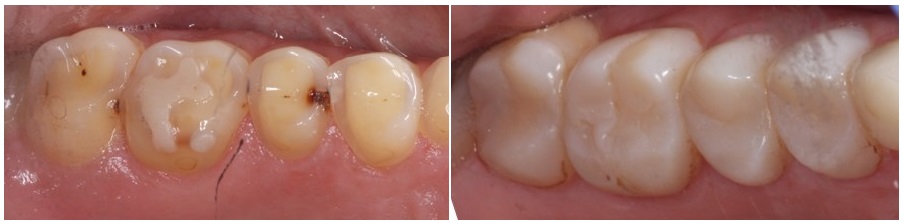

Ακολούθως αρχίσαμε να αλλάζουμε τις μεταβατικές αποκαταστάσεις των πίσω δοντιών, με μικρές αποκαταστάσεις από πορσελάνη, οι οποίες εκτός από το ότι κάλυπτουν την μασητική επιφάνεια των δοντιών κάλυπτουν και την εξωτερική αποδίδοντας ένα πιο πλήρες χαμόγελο, κοντά στις αισθητικές ανάγκες τις ασθενούς μας.

Παλιά σφραγίσματα προεξείχαν πάνω από τα δόντια, ενώ ταυτόχρονα η ασθενής είχε και κάποια δόντια τερηδονισμένα.